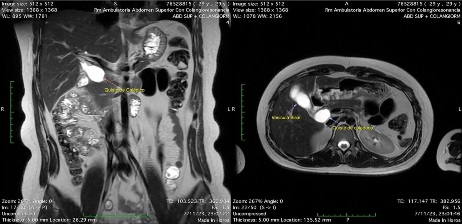

Los estudios se ampliaron con una resonancia magnética de abdomen superior con colangiorresonancia, en la cual se evidenciaron siete pólipos a nivel fúndico de la vesícula biliar de hasta 4 mm de diámetro transverso. Además, se observó una dilatación quística del colédoco extrapancreático de 22 mm de eje transverso y 32 mm de eje longitudinal, sin evidencia de engrosamiento parietal, nódulos intraluminales, realce o restricción patológica, compatible con un quiste de colédoco (Todani tipo Ia). Asimismo, se identificó una dilatación quística del conducto cístico de 8 mm de eje transverso y 13 mm de longitud. El colédoco intrapancreático medía 3,5 mm de calibre con señal homogénea, sin identificar lesiones intraluminales, coledocolitiasis ni lesiones de tipo extrínseco (Figura 3).

Figura 3 Dilatación fusiforme de la vía biliar extrahepática, que corresponde a una dilatación tipo Ia según la clasificación de Todani.